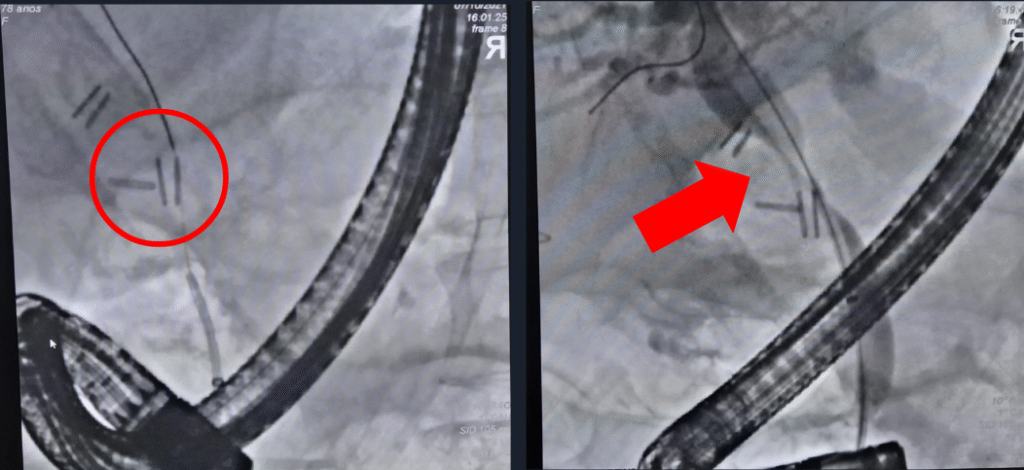

Diante desse cenário, foi indicada terapêutica minimamente invasiva combinada de Colangiopancreatografia retrógrada endoscópica (CPRE) para drenagem da via biliar e drenagem percutânea através de radiologia intervencionista para o bilioma. Ambos bem sucedidos, entretanto CPRE revelou lesão iatrogênica da via biliar (clipagem parcial do ducto colédoco) e coledocolitíase proximal à subestenose, tendo sido procedida drenagem da via biliar com prótese plástica (Fig 3). A drenagem percutânea foi guiada por USG (Fig 4) e aspirado 100ml de liquido bilioso, mantido dreno por 3 dias sem intercorrências.

Fig 3. Imagens dos achados colangiográficas da primeira CPRE: clipes metálicos em via biliar (esq.) e subestenose da via biliar nessa mesma topografia após injeção de contraste (dir.).